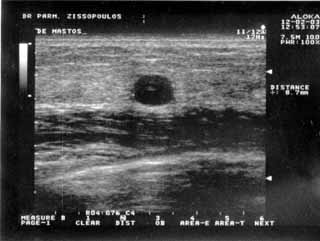

Για την καλλίτερη απόδοση της εξέτασης απαιτείται κεφαλή linear τουλάχιστον 7,5 ΜΗΖ. Ωστόσο και με κεφαλές 3,5 και 5 ΜΗΖ μπορεί κανείς να έχει καλά αποτελέσματα.

Oι τελευταίες 4 απεικονίσεις έγιναν με ειδικό για μαστό ηχοβολέα linear, εναλλασσομένης συχνότητος 7,5-10ΜΗΖ.